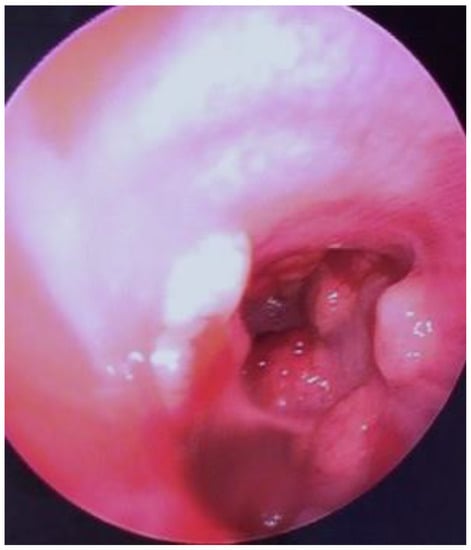

2. Case Report